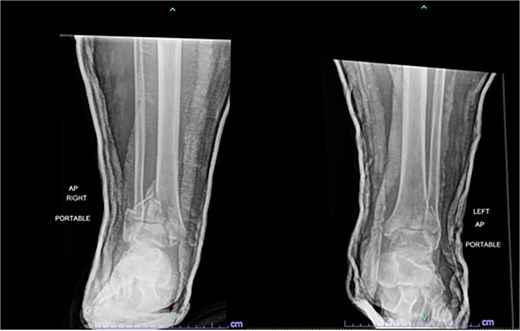

A 38-year-old male with a BMI of 27.5 kg/m2 and a history of alcohol use disorder, paranoid schizophrenia, smoking, and prior bilateral calcaneal fractures treated with ORIF 4 years earlier sustained bilateral pilon fractures after jumping from a third-story window (Fig. 3). He presented to the hospital 5 days after injury.

AP and oblique radiographs of patient 2 obtained after a fall, demonstrating bilateral pilon fractures and retained hardware from prior bilateral calcaneal ORIF.